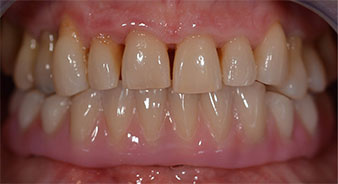

La paciente de 64 años se presentó con una dentición residual compuesta por las piezas dentales 38, 33 y 43 en el maxilar inferior y con una prótesis temporal fijada con ganchos en el maxilar inferior (figs. 1 y 2).

Tras explicarle las distintas opciones de tratamiento, la paciente se decidió por la extracción de la dentición residual en el maxilar inferior, la implantación inmediata y el tratamiento con el método Fast & Fixed (bredent medical), con el que la prótesis dental fijada provisionalmente se atornilla sobre cuatro implantes en el mismo día de la intervención. El objetivo era operar a la paciente el viernes para que el lunes pudiera tomar parte en los exámenes orales para la prueba de acceso a la universidad.